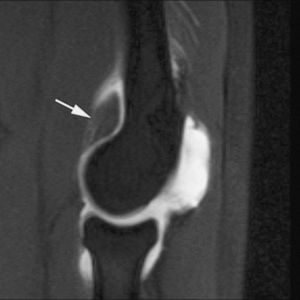

En la actualidad, la RMA es el método más eficaz en la valoración de las lesiones ligamentosas del tobillo. En la fase aguda, su indicación está limitada a aquellos casos en los que el cirujano plantea la realización de una reparación primaria --casos con lesión ligamentosa doble o en deportistas de alta competición--. Sin embargo, su principal indicación es la evaluación de la inestabilidad crónica de tobillo --tiene una sensibilidad del 100% y del 90% para las lesiones crónicas del LPAA y LPC, respectivamente (fig. 9), frente a una sensibilidad del 50% de la RM convencional--20,21.

Fig. 10.--Síndrome de choque antero-lateral. Corte axial de RMA potenciado en T1 que muestra un tejido fibroso irregular ocupando el receso capsular antero-lateral (flechas).